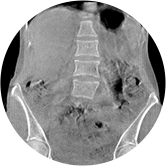

腰椎

FOV 250mm

FOV 350mm